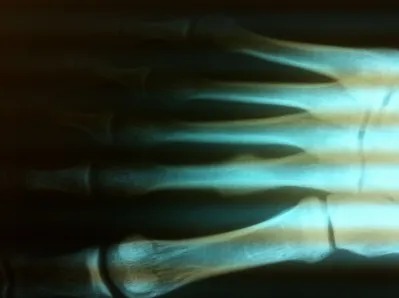

Stress fractures are relatively common to the metatarsal bones. They occur when a patient's activity level over a short period of time has been drastically increased. This can occur in a patient that starts a training season for track or any type of running the sport. It can also be seen in military recruits when they start their training season. Stress fractures of metatarsals are also common in women who change their job and all of a sudden have to wear a high-heeled shoe consistently. This puts stress on the metatarsals and causes a small fracture.

Stress fractures are often a clinical diagnosis as x-rays may be negative initially. The patient would typically experience pain and swelling across the top of the metatarsals. The pain would be mild in the morning. However, would get worse with weight-bearing. When x-rays are negative these problems are still treated as a fracture. X-rays taken 14-21 days after the injury will often show healing of the stress fracture by bone callus along the shaft of the bone.

Diaphysial stress fractures of the fifth metatarsal are more uncommon. These fractures are in an area of the fifth metatarsal bone that has a very poor blood supply. These fractures are often treated with eight weeks nonweightbearing. In rare cases, the fracture does not heal and it may require a small screw to be placed through the bone to allow the fracture to heal. In athletes that do a lot of running or those who have a foot that has a slight turning in of the front part relative to the back part of the foot, surgery may be indicated earlier due to the high propensity for refracture following healing of the primary fracture.

Stress fractures of the metatarsal are also more frequent in some patients that have long metatarsals. Treatment for these stress fractures is often just the use of a boot to unload the metatarsal during the healing process. This would be followed by an orthotic to be placed in the shoe to rebalance the weight-bearing distribution of the metatarsal heads. Long-term prognosis is usually excellent. Rarely do stress fractures fail to heal. Rarely is surgery necessary for these injuries